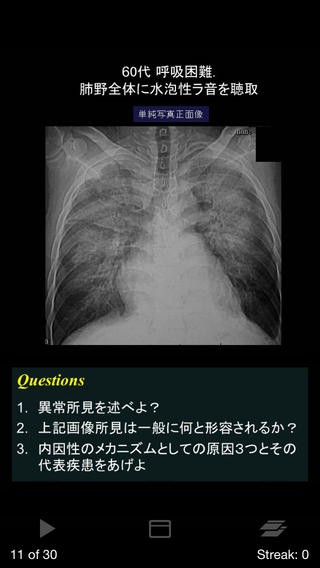

2.胸部60分基礎トレ(720円)

引用元:https://itunes.apple.com/jp/app/id596370666?mt=8&ign-mpt=uo%3D4

肺感染症や、新血管病変などの、胸部の代表的な30疾患の画像に対するQ&Aが、

全6章、60ページにわたって収録されています。

4.胸部X線写真基礎トレ(960円)

シルエットサインを基本とした胸部単純X線写真の読影トレーニングをすることが出来ます。

入門編、基礎編、応用編など、

全4章60ページにわたって収録されています。